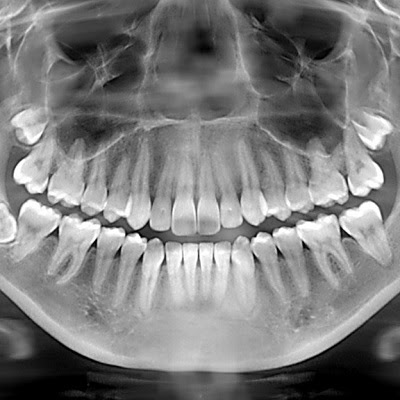

A Dental Panoramic X-Ray (also known as an OPG, or Orthopantomogram) is a type of X-ray that captures a single, wide-angle image of your teeth, gums, jaw, and other structures surrounding your mouth. Unlike traditional X-rays, which require multiple films to view different areas of your mouth, a panoramic X-ray offers a comprehensive view, allowing the dentist to see the entire oral structure in one clear, detailed image. This image provides essential information that can help detect issues that may not be visible during a standard dental exam.

One of the most significant advantages of a Dental Panoramic X-Ray is its ability to detect dental issues that may not be visible to the naked eye. Problems like:

- Cavities between teeth (often hidden from traditional X-rays)

- Impacted teeth, especially wisdom teeth

- Jawbone abnormalities such as bone loss or cysts

- Infections or abscesses in the jaw

- Tumors or growths that may be developing

These are all conditions that a panoramic X-ray can reveal early, which allows for faster treatment and prevention of further complications. In a dynamic city like Dubai, where dental procedures and treatments are often highly specialized, early detection is invaluable. It allows your dentist to address problems before they become more serious, preventing the need for more invasive treatments.